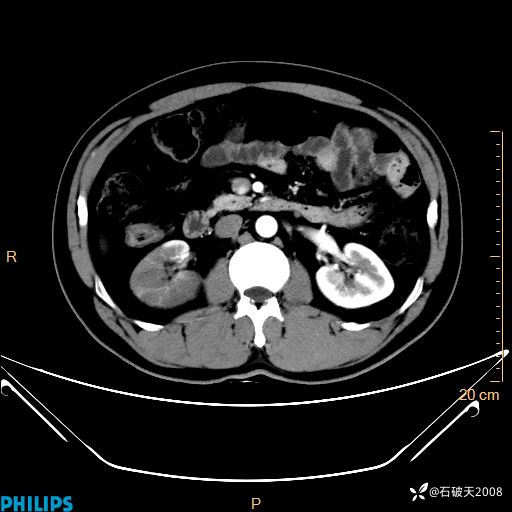

MIP